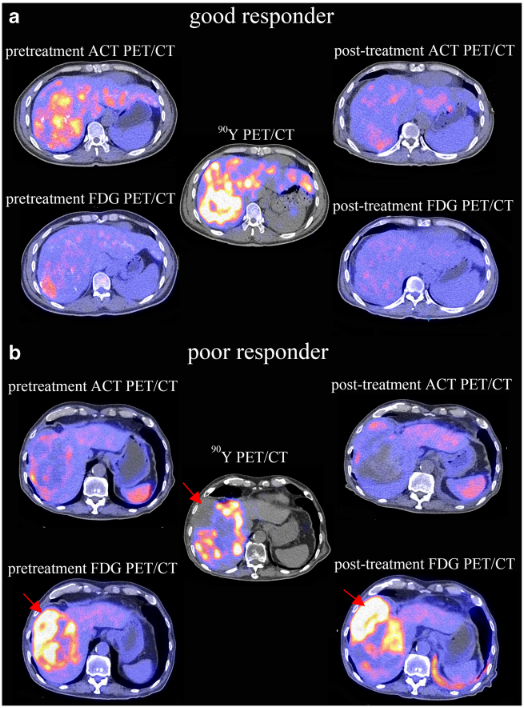

療診合一 (Theranostics)

11C標記醋酸和18F標記葡萄糖與90釔肝腫瘤體內放射治療的同步互動關係